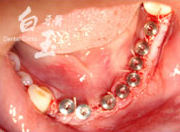

植入植體

治療後

治療中